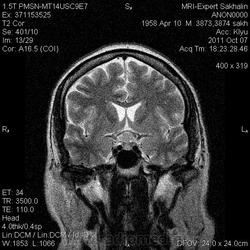

Аденома гипофиза

Вот такая аденома гипофиза сегодня.Мужчина с жалобами на снижение зрения.

постконтраст

Мне кажется что это все же не аденома, может глиома хиазмы ? (воронки гипофиза)? Или еще какое-нибудь объемное образование.... Что то меня смущает, еще не поняла что, но В любом случае наверное я бы однозначно не писала что это аденома, а выставила бы весь диф. ряд.

Танюша, обычно пишем "образование хиазмально-селлярной области"

Присоединяюсь к последнему коментарию, все таки откуда растет по моему мнению трудно однозначно сказать, лучше себя обезопасить написав "объемное образование хиазмально-селлярной области"